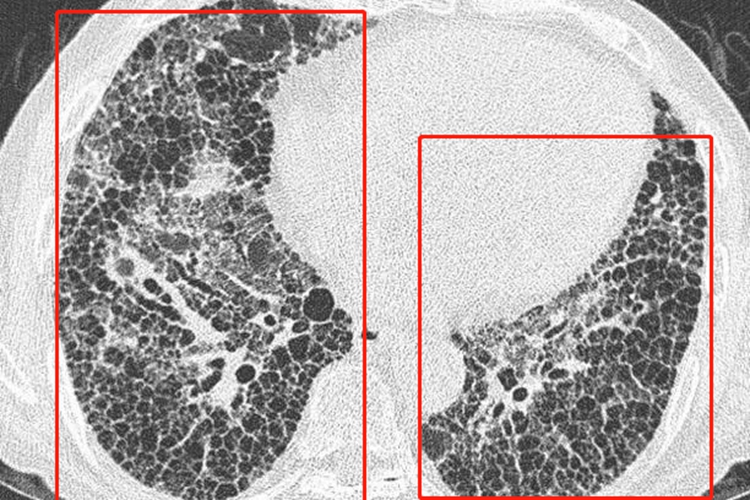

呼吸系统

呼吸道黏膜受累可引起鼻腔干燥、结痂、鼻出血、鼻中隔炎和萎缩性鼻炎,以及咽喉干燥、声音嘶哑、干咳、痰液黏稠等。检查可见肺间质纤维化,偶见胸膜炎。肺功能可有弥散性功能障碍、限制性或阻塞性通气功能障碍。另有小部分人群出现肺动脉高压和肺纤维化。